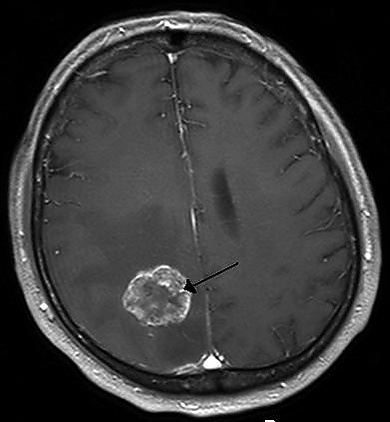

К обязательным методам обследования относятся определение активности сухожильных рефлексов, проверка тактильной и болевой чувствительности. Диагностические мероприятия могут быть расширены в зависимости от жалоб больного и с целью дифференциальной диагностики. Так, например, если больной отмечает нарушения координации, следует провести пальце-носовую пробу, проверить устойчивость в позе Ромберга. Если возникает подозрение на опухоль мозга, то больной направляется на компьютерную (КТ) или магнитно-резонансную томографию (МРТ). МРТ с контрастным усилением является «золотым стандартом» в диагностике опухолей головного мозга[5]. При обнаружении на томограмме объёмного образования решается вопрос о госпитализации больного в специализированный стационар.